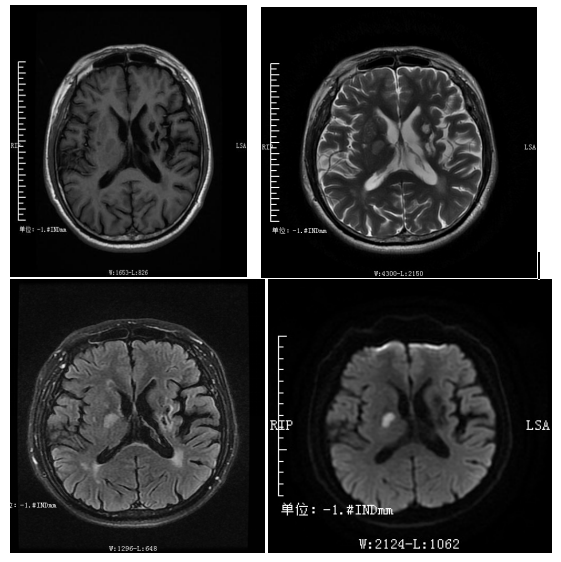

急性腔隙性脑梗死

SWAN(磁敏感成像)动静脉畸形